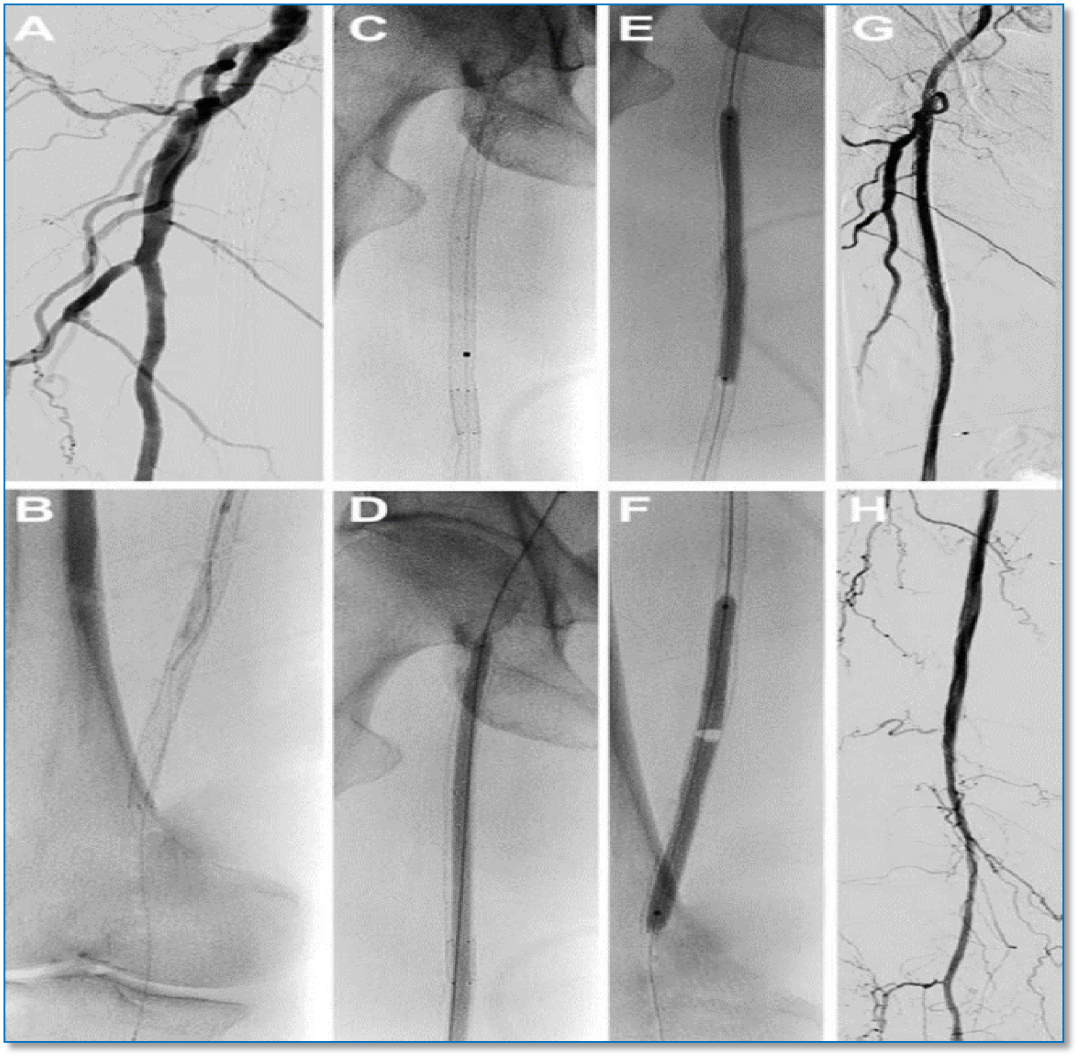

★ 病例基本情况

84岁女性患者,因"右足背、拇趾溃疡半年,支架植入术后4年余"就诊。患者4年前因下肢缺血行支架植入术,近期症状复发加重。

图:术前CT

★ 术前评估

血管造影显示股腘动脉长段支架内再狭窄,伴有严重钙化。

★ 术中造影

图:术中造影

★ 激光消融

图:使用2.3mm导管,参数设置从45mj/mm²、45Hz开始,逐步增加至60mj/mm²、60Hz。

★ 球囊扩张

依次使用不同规格球囊进行扩张

Saber 2--200mm球囊

Saber 5--300mm球囊

Reewarm 5--220mm球囊

Saber 2.5--150mm球囊

★ 术后结果

血管造影显示管腔明显改善,血流恢复良好

图:术后造影